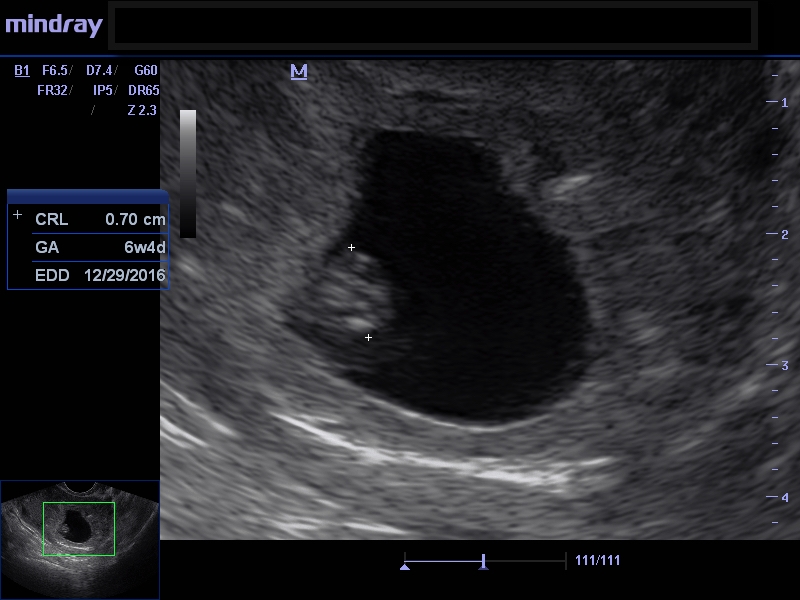

UPDATE!!! The ER doctors in Maine are complete morons. So our OB was amazing - they worked us in first thing this morning. We saw little baby blob again, and it has a heartbeat of 123. Measuring just three days short of my estimate based on ovulation, which is perfectly normal. They did find a subchorionic hemorrhage, which has been causing the bleeding. They're doing lab work to test my progesterone to see if I need supplements, but he said that most of these will resolve their own. We have another ultrasound in two weeks to check on the progress.

So let's talk about the complete idiocy of the ER doctors. They told me the baby "wasn't where it needs to be developmentally". The OB said that all you can check for at this point is cardiac function - which is what I had thought - that we can't really see any anatomy yet. He said, "I won't even tell you all of the crazy things they said in their message to me, but they claimed that the baby's heart was on the outside of its body." This would be a one in a million odds unicorn of a pregnancy, and he said you CAN'T SEE THAT if it were the case until around 12 weeks. He was baffled that they seemed to so confident in their analysis of the situation. They also DIDN'T SEE the subchorionic hemorrhage, which was so evident on the screen that I thought it was the baby at first.

Good luck with everything. Last week my baby had a heartbeat of 113 and measures 6w4d and doctor wasn't worried. So 120 sounds great! Also baby looked like a blob and I could mostly see the yolk sac with a flicker, which was the heartbeat. Please keep us updated. We are all hoping for good news.